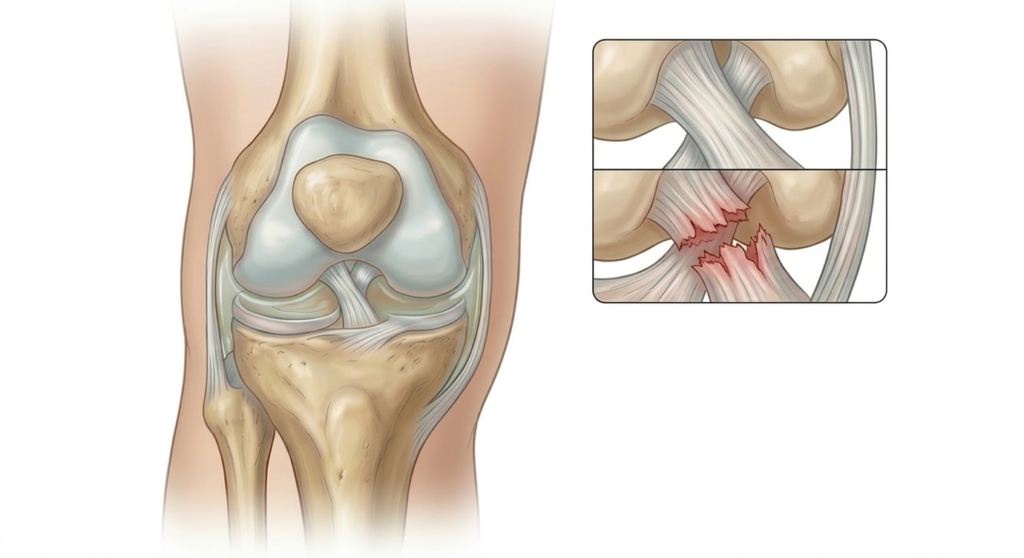

Il Legamento Crociato Anteriore (LCA) e il Legamento Crociato Posteriore (LCP) sono i più importanti stabilizzatori del ginocchio impedendo, rispettivamente, la traslazione anteriore e posteriore della tibia rispetto al femore. Le rotture del LCA e, con minor frequenza del LCP, sono tra i traumi sportivi più comuni e si verificano a seguito di eventi distorsivi diretti o indiretti con rotazioni forzate o eccessiva estensione del ginocchio.

Gli sport in cui sono più frequenti questi meccanismi traumatici sono il calcio, lo sci e la pallacanestro e la gravità della lesione, parziale o totale, così come la presenza di lesioni associate dei menischi, dei legamenti collaterali e della cartilagine, sono direttamente correlati all’intensità del trauma. In occasione della rottura del LCA il paziente riferisce, solitamente, la sensazione di “crack” articolare e come se il ginocchio uscisse dalla sua sede.

Successivamente i sintomi principali sono il dolore, il gonfiore e la difficoltà a muovere l’articolazione per lasciare il posto dopo qualche settimana ad una sensazione di instabilità articolare con possibili episodi di cedimento. La diagnosi anche in questo caso si avvale di test specifici e di esami strumentali; tra questi ultimi l’esame con la miglior capacità di evidenziare la rottura legamentosa e le eventuali lesioni associate è senza dubbio la RMN.